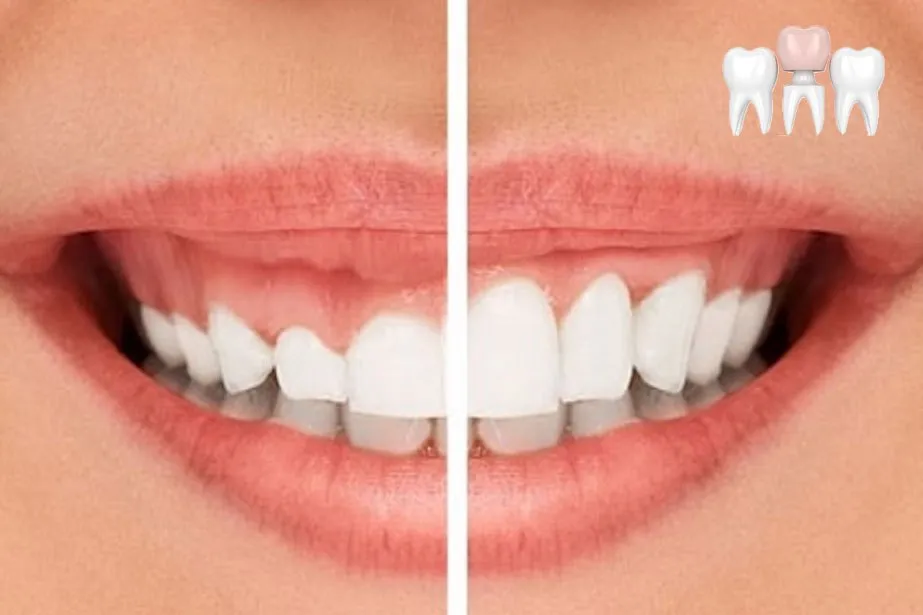

Hiện tượng răng sứ bị hở là hiện tượng rất nhiều người gặp phải. Tuy nhiên, rất ít người nhận ra được cho đến khi nó trở